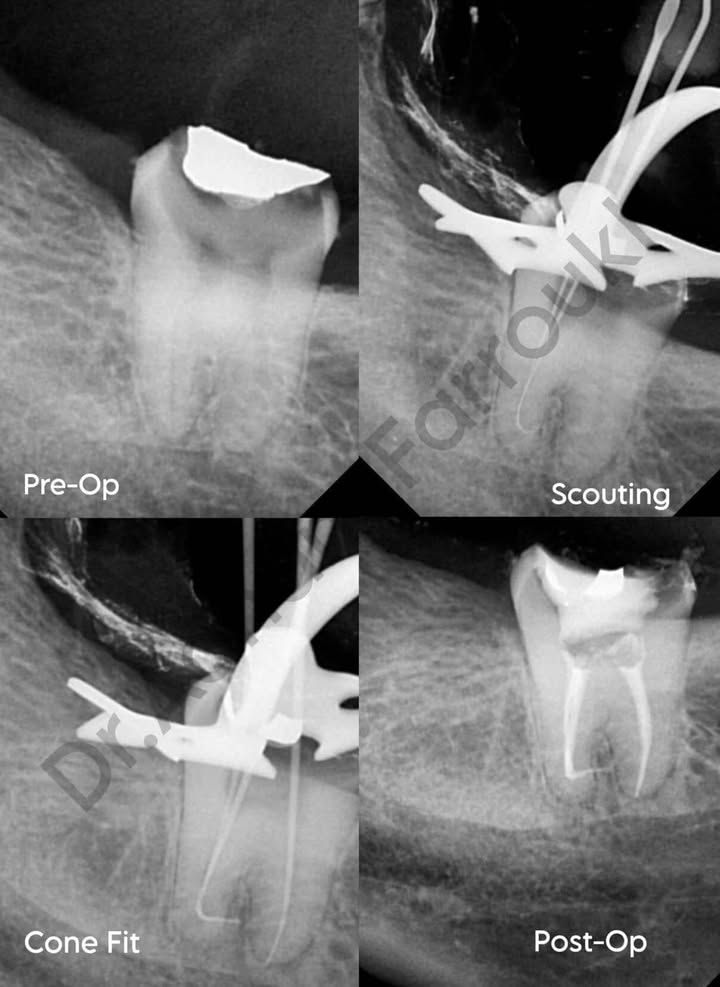

Tooth: #47

Diagnosis: Symptomatic Irreversible Pulpitis

This advanced endodontic case involved Tooth 47 diagnosed with symptomatic irreversible pulpitis. The mesial canals were severely constricted with extreme curvatures, presenting a significant challenge in achieving patency and managing the high risk of apical blockage.

- Removal of Previous Restoration

The old restoration was completely removed to allow proper access. - Coronal Preflaring

Coronal preflaring was performed using EZ Shaper Pro (EZx) files. - Scouting & Patency Achievement

Manual scouting was carried out with pre-curved hand files up to size 15. When apical blockage was encountered, patency was carefully searched for after appropriate pre-curving of both manual and rotary files. - Final Canal Preparation

Final shaping of the canals was safely completed using EZ Shaper Pro (EZ2) files. Due to the extreme curvatures, enlargement was kept conservative. - Obturation

Final obturation was performed using the single cone technique with bioceramic sealer.